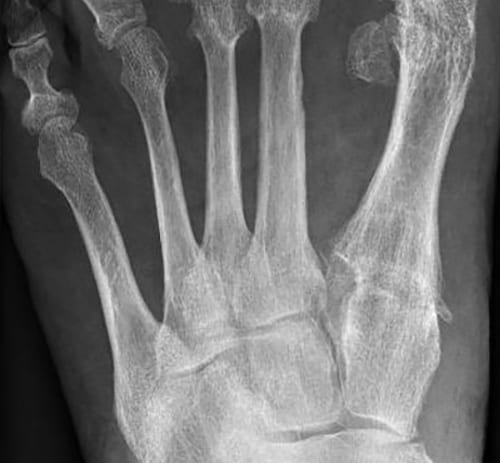

X-ray postoperatively ap

Correction by TMT I osteotomy and lapidus arthrodesis with 2 Shark Screw® grafts